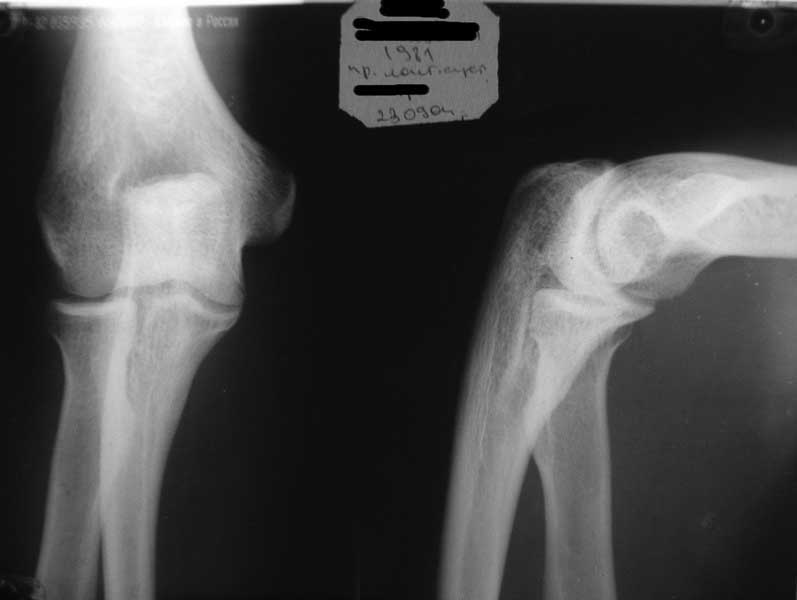

Уважаемые коллеги!Требуется ваша помощь. На консультацию обратился пациент 30 лет с жалобами на ограничение активных движений в левом плечевом суставе. Пассивные – в полном объеме. Со слов – имела место некая родовая травма. К тому же отмечается незначительный дефицит иннервации n.radialis (снижение «силы» разгибателей-сгибателей в кистевом суставе и отведения 1 пальца; неврологи никакого специфичного лечения не назначают). Также имеется контрактура локтевого сустава: сгибание в полном объеме, разгибание 150 градусов, супинация в пределах 7 градусов. Функция конечности в принципе устраивает. Скелетных травм в анамнезе нет. Вопрос: есть ли смысл заниматься какими-либо реконструкциям на плечевом суставе и как можно улучшить функцию скомпрометированных суставов? Заранее всем благодарен

Уважаемый Михаил, у Вашего пациента вероятнее всего "родовая травма" была скелетной, т.е. во время родовспоможения произошел эпифизеолиз дистального эпифиза плечевой кости. Клинически это проявляется некоторым непродолжительным ограничением подвижности в конечности, консолидация (учитывая возраст) проходит достаточно быстро (7-10 дней). Бывает, что при выписке из роддома ребенка уже ничего не беспокоит. Имеющийся на снимке локтевого сустава варус дистального метафиза плеч кости может быть результатом такой травмы. Что касается неврологии, при подобной травме может произойти повреждение лучевого нерва, но это как правило следствие больших смещений эпифиза (заметили бы сразу). Второй вариант - роды столь травматичны, что повредили и плечевое сплетение - проксимальный паралич Эрба, который либо не распознали, либо плохо лечили, в итоге ограничение амплитуды подвижности в плечевом суставе.